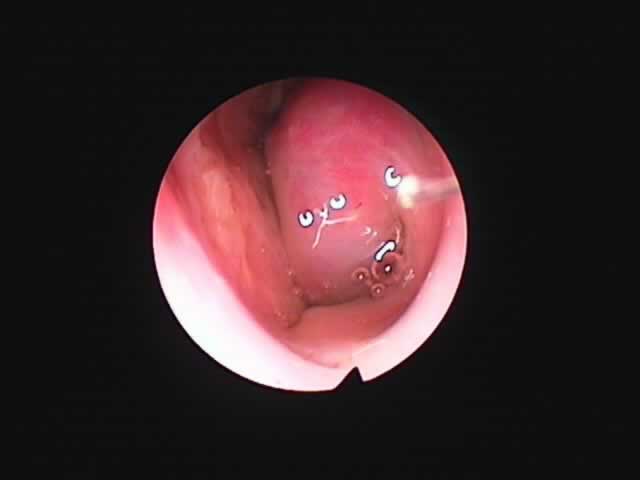

| 左扁桃術直後(31歳男性,6月9日) 数カ所針電極を刺入 | 白い部分が変性部位(6月11日) | 右扁桃術直後(7月7日) |